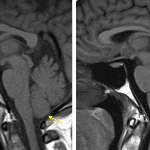

- Empty, expanded sella

- Low-lying cerebellar tonsils without peg-like morphology or significant crowding at the foramen magnum

- Idiopathic intracranial hypertension (IIH)

Constellation of findings including bilateral posterior scleral flattening, tortuous intraorbital optic nerves, empty expanded sella, bilateral distal transverse sinus stenosis, and low-lying cerebellar tonsils is typical for idiopathic intracranial hypertension (IIH). Recommend correlation with CSF pressure analysis.